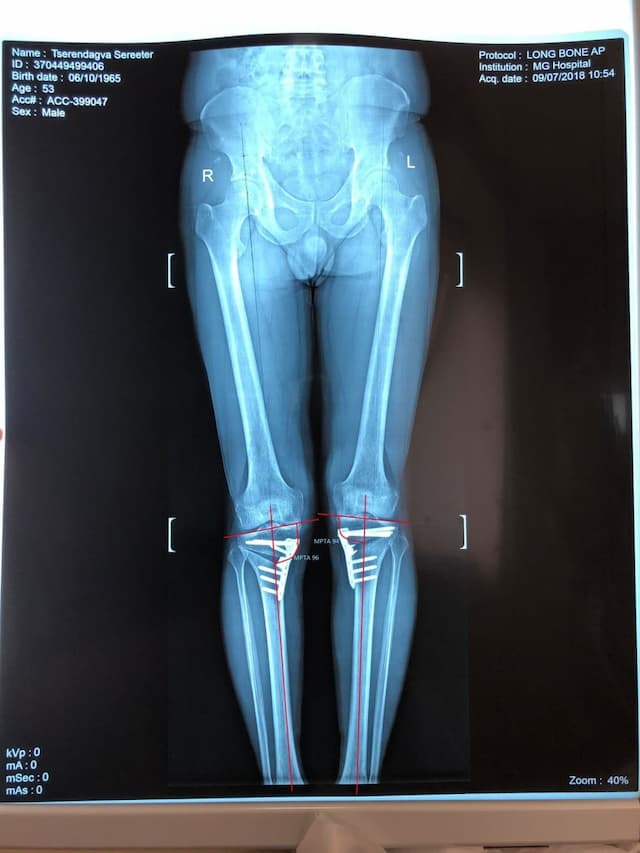

Биеийн жингийн шугамыг мэс заслын өмнө болон мэс заслын дараа хэмжсэн байдал

Эмчлүүлэгчийн өвчний явц, үе шат, өвдөгний үений өвдөлтийн хэлбэр, хөдөлгөөний далайц зэргийг сайтар нягталсны үндсэн дээр мэс заслаар биеийн жингийн шугам, шаантны дотор дээд өнцөг, ясны хугарлын цэг, тэлэгдэх өнцгийг нарийн тохируулснаар хүссэн үр дүндээ хүрэх боломжтой.

Шаантны дотор дээд өнцөг мэс заслын өмнө баруун хөлд 84o, зүүн хөлд 82o байсан бол мэс заслын дар аа баруун хөлд 96o, зүүн хөлд 94o болж засагдсан байдал.